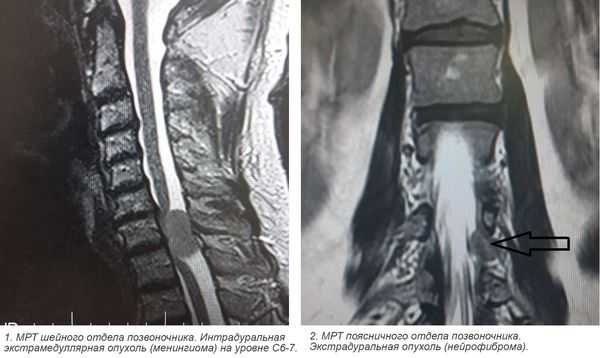

Экстрамедуллярные опухоли спинного мозга

Экстрамедуллярные опухоли — спинальные новообразования, не прорастающие в спинной мозг, а локализующиеся около него. Могут располагаться над и под твердой мозговой оболочкой. Обычно экстрамедуллярные опухоли начинаются с признаков поражения спинального корешка, потом происходит сдавление спинного мозга с поражением половины, а затем всего его поперечника. Скорость развития клиники зависит от вида опухоли. В диагностике наиболее информативна МРТ, при невозможности её проведения — КТ-миелография. Лечение хирургическое — радикальное удаление. В случае злокачественных новообразований проводится химио- и радиотерапия.

Клиническое значение имеет классификация экстрамедуллярных опухолей по виду. Так, среди субдуральных образований более часто встречаются менингиомы, невриномы и нейрофибромы. В совокупности они занимают около 80% опухолей экстрамедуллярной локализации. Эпидуральные новообразования могут быть представлены гемангиомой, липомой, хондромой, остеомой, хондробластомой. Предположительно определить вид опухоли можно при помощи методов нейровизуализации, однако точно его установить позволяет лишь гистологическое исследование.

- Менингиома— опухоль мягкой оболочки До 70% случаев связано с расположением в грудном отделе, около 20% - в шейном. Возникает субдурально, но в 10-15% имеет эпидуральную составляющую. В 2 раза чаще встречаются у женщин, что связывают с влиянием на их рост женских гормонов.

- Нейрофиброма — чаще поражает чувствительные (сенсорные) корешки. Диффузно прорастает спинальный корешок, вызывая его утолщение. Поэтому её удаление возможно только путем полного пересечения корешка. Нейрофиброма может трансформироваться в злокачественную нейрофибросаркому. Риск малигнизации повышен у пациентов с нейрофиброматозом.

- Томография. Наиболее достоверным методом, визуализирующим экстрамедуллярные опухоли является МРТ позвоночника. Она дает возможность определить точное расположение, распространенность, форму опухоли, предположить ее вид, оценить степень спинальной компрессии. При наличии противопоказаний к МРТ альтернативным методом выступает КТ-миелография.